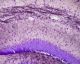

Hito CryoMyelinStain™ Kit (Gold phosphate complex Myelin Staining Kit / Black Gold II Staining Kit) is made in a ready-to-use format and offers high quality, rapid staining of myelin/myelinated axons on frozen sections (mounted or floating). This kit has many advantages compared to the traditional Luxol fast blue staining method which is time-consuming, requires usage of 40-56°C incubator, and usually has low yields of stained myelin fibers and unreliable results. In addition, the long time high temperature incubation process of the frozen sections may cause sections felling off from the slides. Hito CryoMyelinStain kit offers a simple solution to these problems. The procedures are simplified and the processing time is greatly reduced. Users can use mounted sections or floating sections at room temperature. This kit delivers stable and improved staining quality. It has been proven to be extremely reliable and sensitive for demonstrating the morphological details of myelin fibers.

Myelin is essential for the proper functioning of the nervous system. Demyelination impairs the conduction of signals in the affected nerves, causing impairment in sensation, movement, and cognition. Currently no cure exists for demyelinating diseases and myelin repair is an active research field. Hito CryoMyelinStain™ Kit allows sensitive localization and visualization of the myelin fibers, thus offers a fast and reliable way to determine the extent of  demyelination [Sample Images: experimental allergic encephalomyelitis (EAE)].